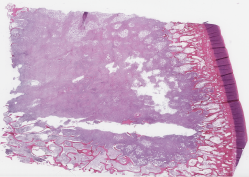

Category Train Validation Image Example

(Count) 1271 317 [Uncaptioned image]

(No-Count) Lipomas 703 176 [Uncaptioned image]

(No-Count) Non-neoplastic lesions 400 100 [Uncaptioned image]

(No-Count) Skin punch biopsies 180 45 [Uncaptioned image]

(No-Count) Skin&subcutaneous tissues 522 131 [Uncaptioned image]

Table 1: Biopsy slide classification data